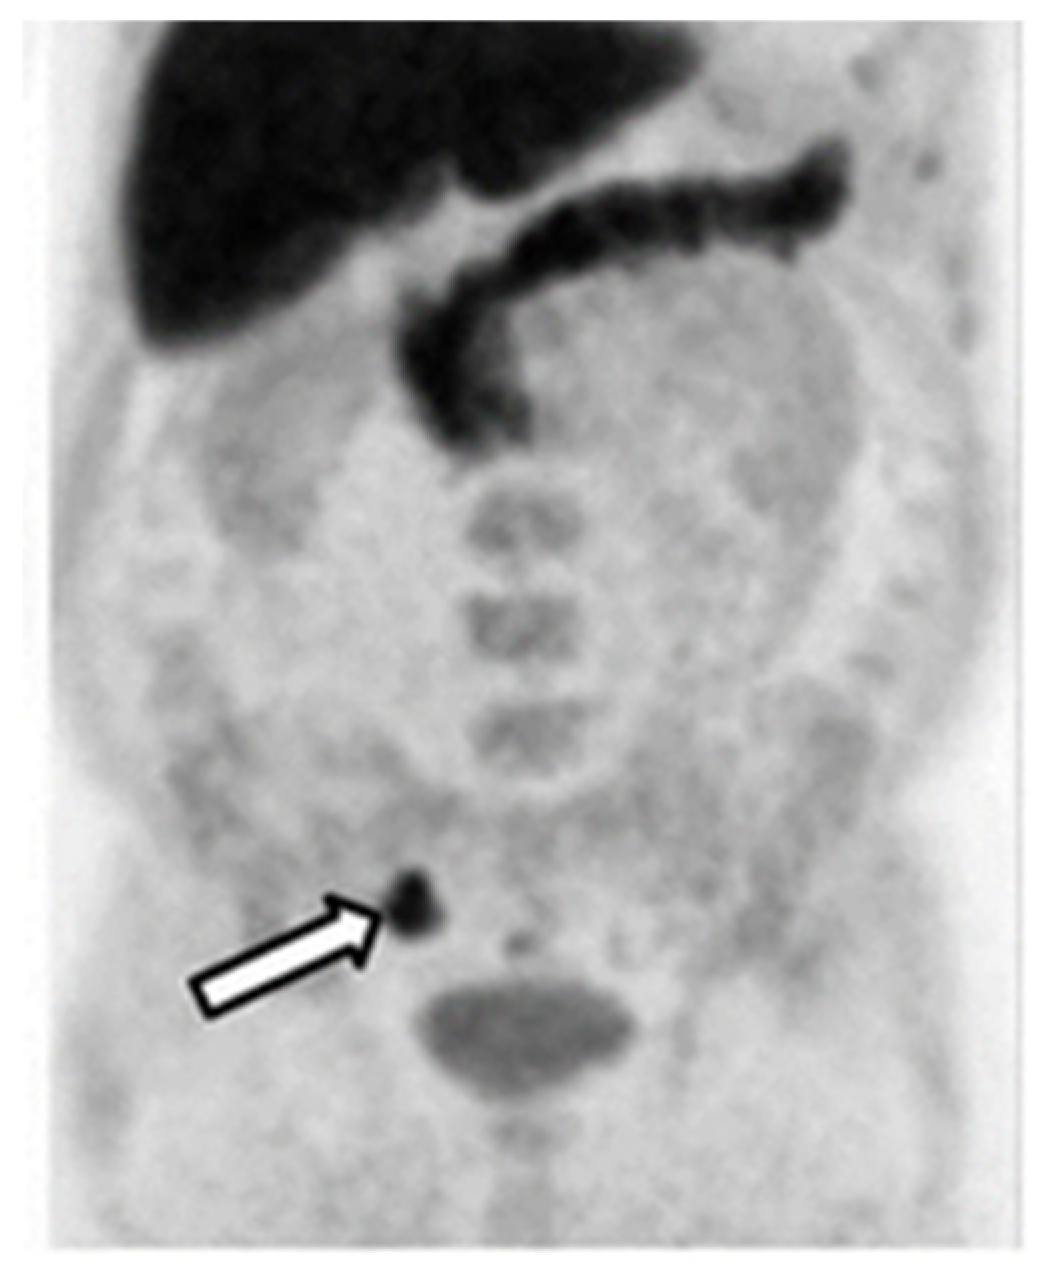

Figure 3. [11C]Choline PET/CT image of a patient with an adenocarcinoma of the prostate (white arrow). This research was originally published in the Journal of Nuclear Medicine (JNP) [29].

However, the detection rate for PCa recurrence dropped to 55% when [11C]choline was applied to a large cohort of PCa patients (3203 patients) [30]. The detection rate for [11C]choline was found to be associated with PSA values. A detection rate of 73% was found for patients with PSA levels above 2.0 ng/mL [26], but this rate dropped to only 27% for patients with PSA levels below 1.16 ng/mL [30] and further decreased for patients with even lower PSA levels [31]. It is still unclear to what extent [11C]choline PET/CT imaging can be useful in the diagnosis of BCR PCa, especially if biochemical relapse for PCa patients after an RP is defined as patients having PSA levels higher than 0.2 ng/mL. However, despite the low detection rate, a negative [11C]choline scan can predict a longer OS after a prostatectomy and ADT [31,32]. [11C]Choline PET/CT may be useful in monitoring patients after primary curative therapy and in the detection of BCR, but unsuitable for the primary diagnosis of PCa [32].